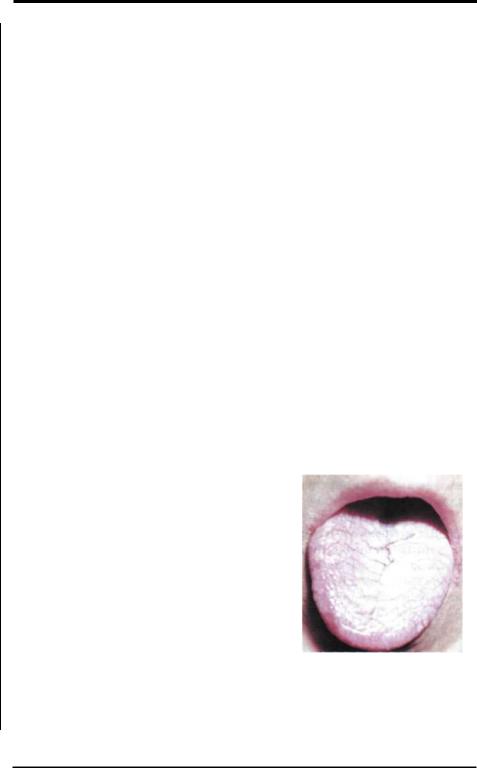

Рис.7-10: Поражение |

Каплевидный |

парапсориаз. (Рис.7-10). |

языка |

при |

каплевидном |

||||||

Впервые описан Ядассоном в1894 году. Пред- парапсориазе Ядассо- |

левания в полости рта можно наблюдать многочисленные беловатые, резко очерченные папулы. Иногда из-за мацерации на папулах возникают геморрагии и некротизация в центре, в связи с чем они напоминают пустулы. После разрешения высыпаний почти всегда остаётся пигментация и нередкомелкие рубчики. Лечение антибиотики, УФО и ПУВА-терапия